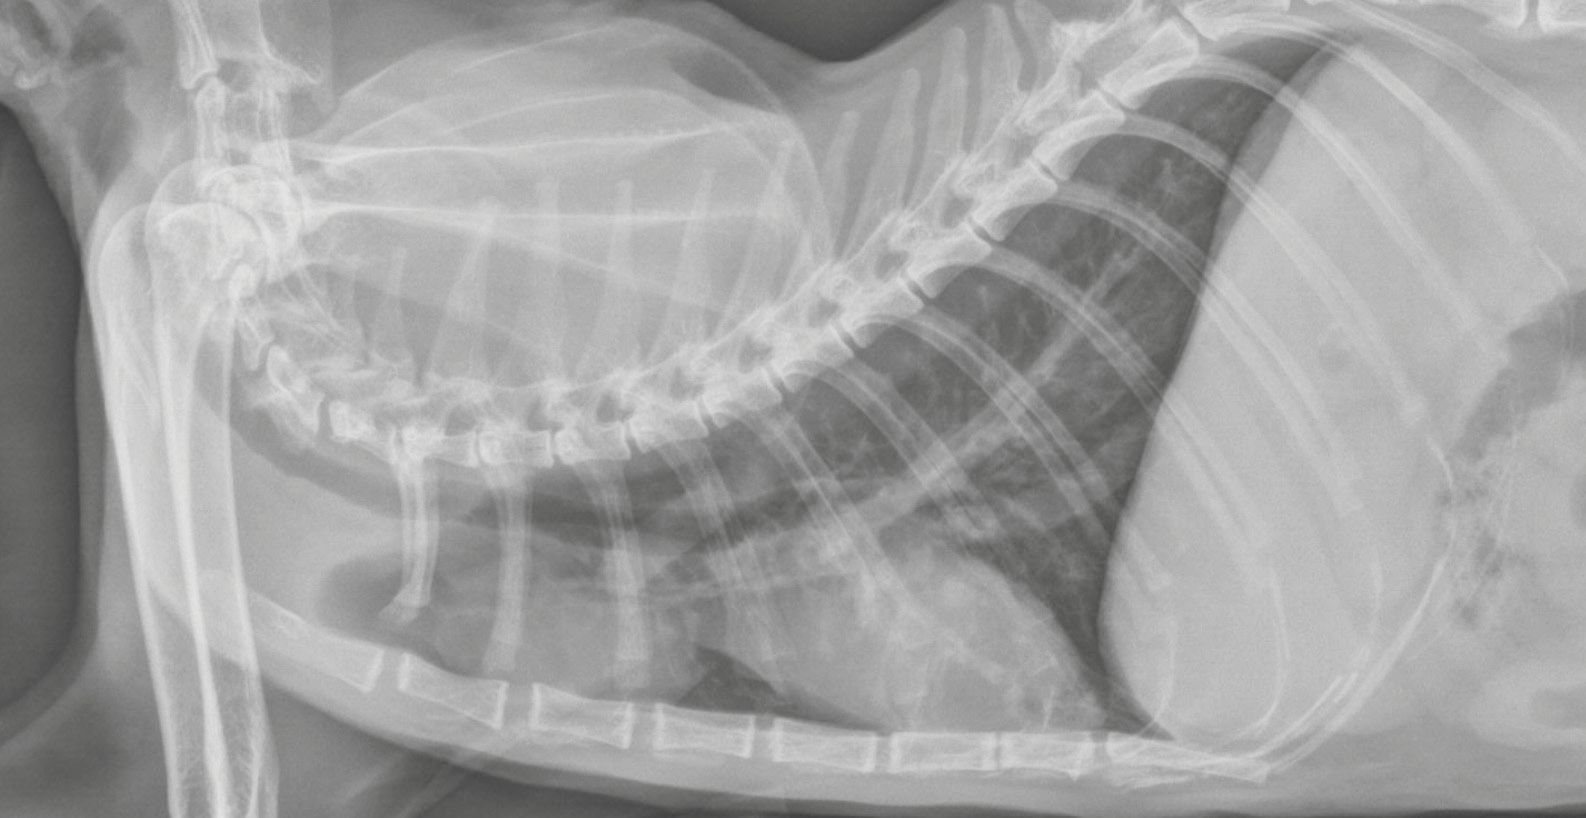

Source: empowhimhfq.pages.dev Le lymphome médiastinal félin Royal Canin , Le lymphome peut se présenter sous 5 formes cliniques chez le chat : • Le lymphome médiastinal. C'est une forme très rare de lymphome chez le chat et elle est associée au virus de la leucémie féline